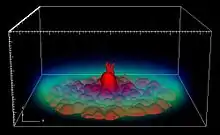

VR Technique

Entire volume transparence of the object is visualized using VR technique. Images will be performed by projecting rays through volume data. Along each ray, opacity and color need to be calculated at every voxel. Then information calculated along each ray will to be aggregated to a pixel on image plane. This technique helps us to see comprehensively an entire compact structure of the object. Since the technique needs enormous amount of calculations, which requires strong configuration computers is appropriate for low contrast data. Two main methods for rays projecting can be considered as follows:

- Object-order method: Projecting rays go through volume from back to front (from volume to image plane).

- Image-order or ray-casting method: Projecting rays go through volume from front to back (from image plane to volume).There exists some other methods to composite image, appropriate methods depending on the user's purposes. Some usual methods in medical image are MIP (maximum intensity projection), MinIP (minimum intensity projection), AC (alpha compositing) and NPVR (non-photorealistic volume rendering).